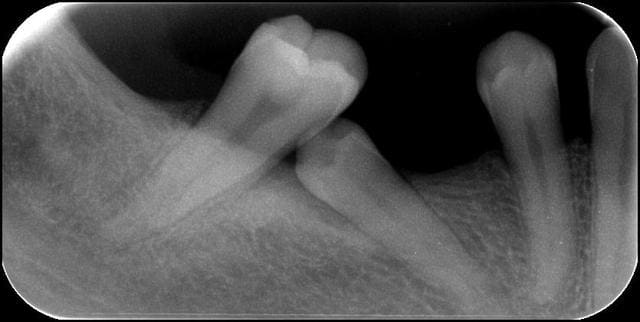

Malposition 45 fe0vb1 - Eugenol

C'est une partie de Mikado en fait, il faut en sortir une sans faire bouger l'autre !

surtout ne pas toucher la 5 sinon la 7 tombe